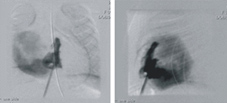

混合手術前,無肺動脈顯影

導管帶入金屬導線刺穿閉鎖之肺動脈瓣